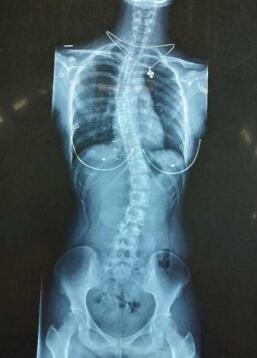

6月底,betway在线登陆产科接诊了一位“特殊”的准妈妈小欣(化名),和其他即将临盆的准妈妈不同,小欣一脸愁容,原来她有严重的脊柱侧弯,该症无疑给有剖宫产手术指征的她带来很大的困扰。

严重的脊柱侧弯再加上孕晚期体重达到了115公斤,为了让宝宝更加安全、顺利地出生,小欣连续咨询了多家医院后,得到的答案却都是建议在全身麻醉下进行剖宫产手术,小欣很失望。

小欣脊柱侧弯